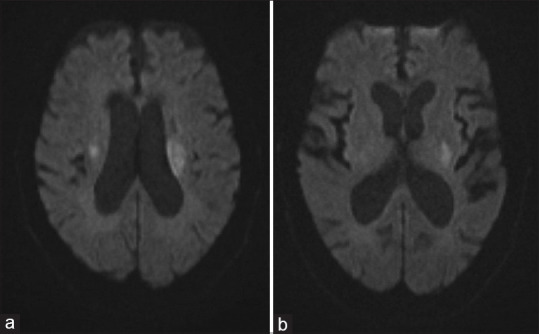

Abstract Image